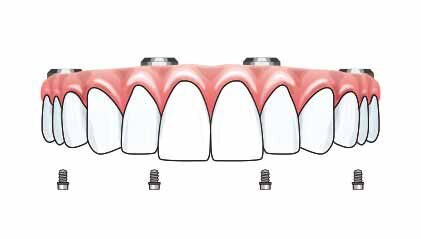

オールオン4

ザイゴマ0

ザイゴマ2

ザイゴマ4

従来のインプラント治療法との大きな違いは、4本のインプラントだけで12本の人工歯を支えるということです。また、骨移植や骨造成手術を必要としません。これはつまり、

• 体への負担が少ない

• 治療費を抑えられる

ということを意味しています。

そして、オールオン4の最も画期的な点は、

• 1日で固定式の歯に

になることです。つまり、前歯がぐらぐらでも、歯がボロボロでも、手術当日に仮歯が入り、噛めるようになるということです。